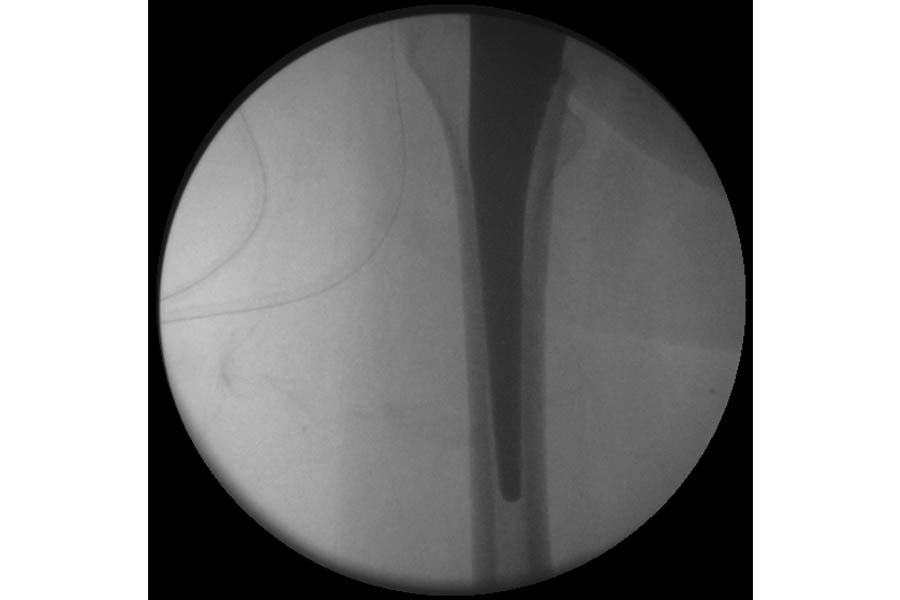

Complicated Joint Replacement

Case 1